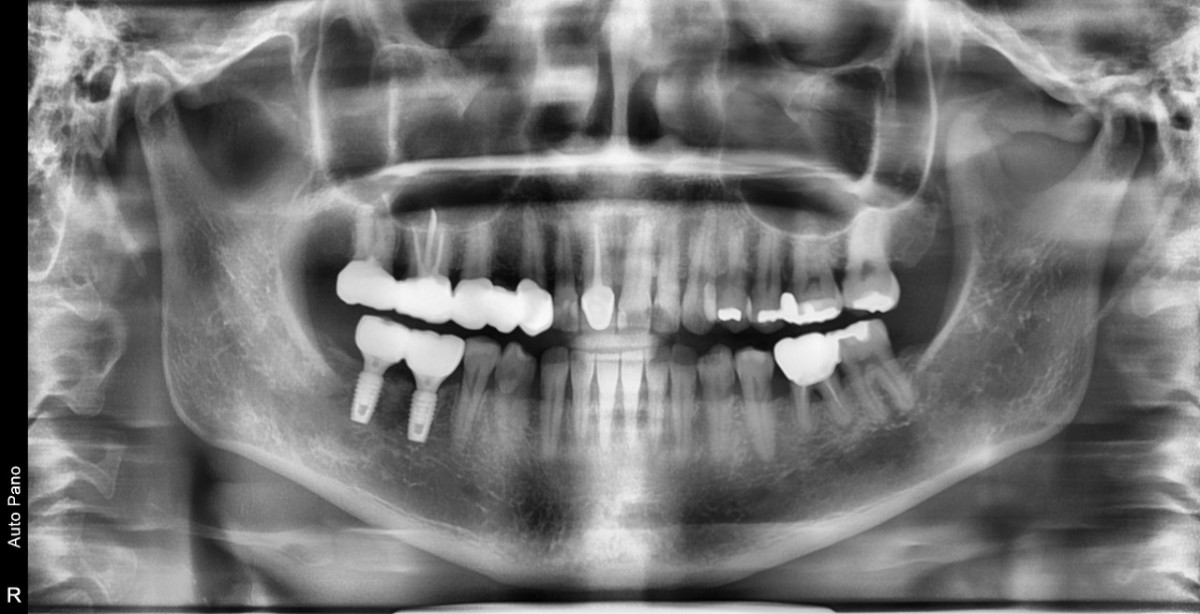

Immediate placement of an implant (Arum Dnetistry NB1, 5*8.5)

A 51-year-old patient complained of an

old-crowned molar. The lower left molar had a gold crown, and the margin showed discoloration indicative of inner caries. Also, it had furcation-involved periodontitis

with an apical lesion.

Extraction and immediate placement of an implant.

▲Arum Dentistry NB1 fixture (5*8.5mm)